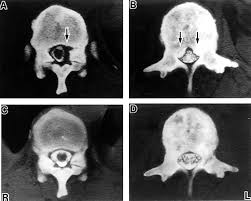

Metastatic Disease Of Spine Pathology Orthobullets

Metastatic Disease Of Spine Pathology Orthobullets from upload.orthobullets.com